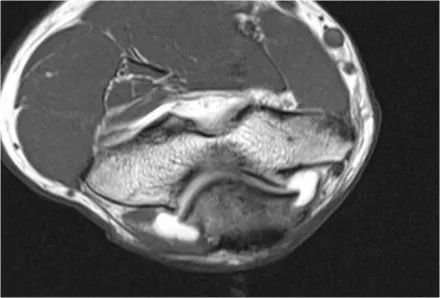

当我们看轴向扫描时,我们可以欣赏巨大的骨赘形成。请注意,尺骨神经(蓝色箭头)紧邻这些骨赘,这些可能指示尺神经出现病变。